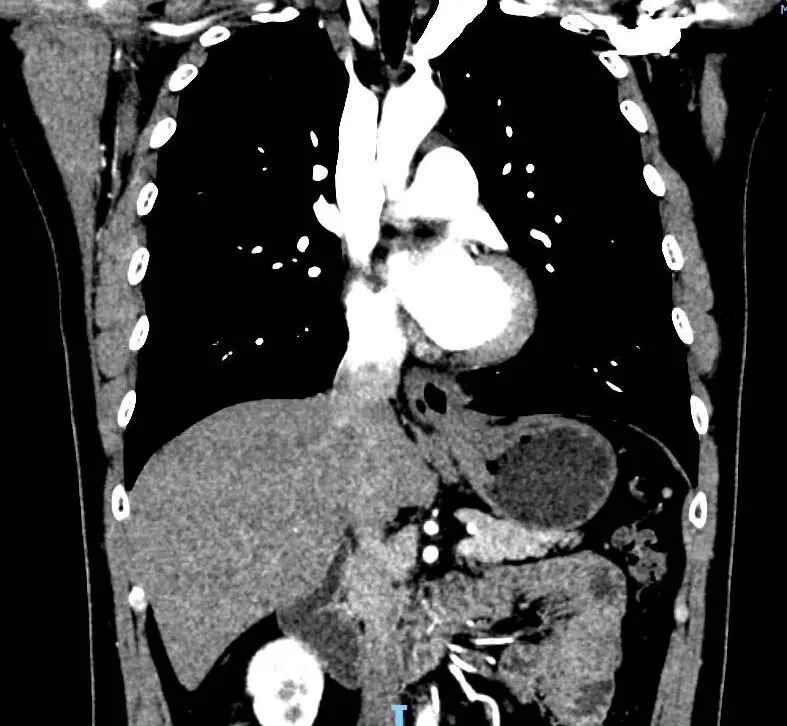

术前CT提示食管裂孔疝复发

经过系统检查,雷先生被确诊为食管裂孔疝术后复发。复发疝手术难度较大,主要面临两大挑战:一是既往手术导致的腹腔广泛粘连,解剖结构如同“迷宫”;二是二次修复需在瘢痕组织中精准分离,避免损伤食管或血管神经。